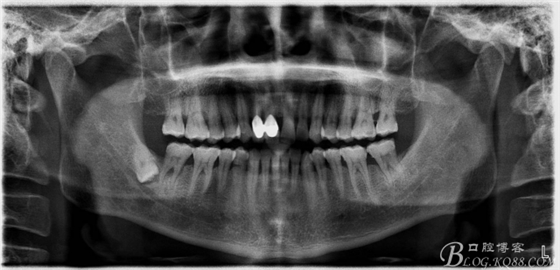

一、術(shù)前全景片影像:

48未萌出,47遠(yuǎn)中可探及深約7mm的牙周袋。頰側(cè)47、48之間牙齦紅腫,有少量血性滲出。X線根尖片顯示:48牙冠反轉(zhuǎn)倒置,47遠(yuǎn)中牙槽骨吸收明顯。CBCT顯示:48牙冠近中面位于下頜管內(nèi)。